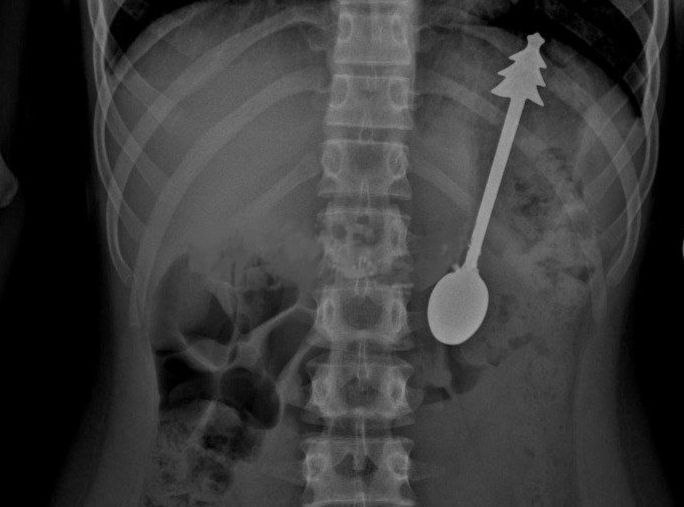

Специалисты сделали экстренный рентген и обнаружили инородное тело в области желудка, сообщили в областной детской больнице.

Там ему провели операцию по извлечению чайной ложки длиной в 14 сантиметров.